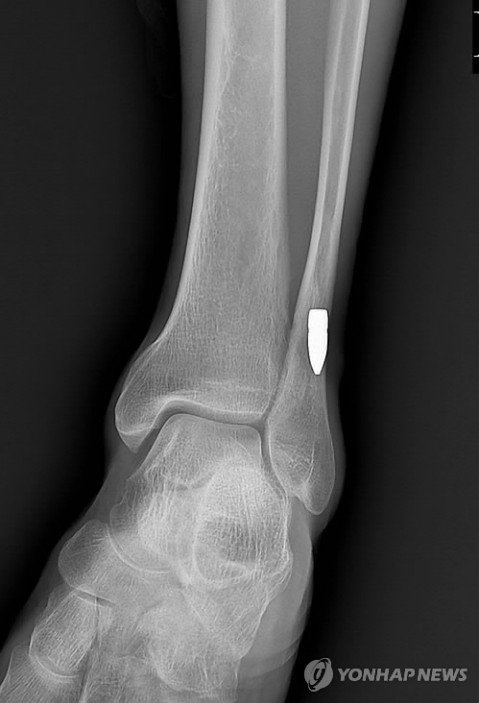

2014년 2월 일산동구 식사동 자동차재활용센터 신축 공사장에서도 일하는 50대가 왼쪽 발목에 총상을 입었다.

발목에 박힌 K2 소총 탄두 (출처=연합뉴스)